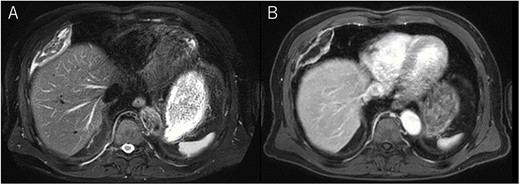

A 72-year-old man with a history of hypertension and left renal cancer (Stage I) was referred to us with a mass in the right chest wall on post-operative follow-up chest computed tomography (CT) for renal cancer. He had a smoking history of 20 pack-years and had no exposure to environmental fumes or dust. Physical examination results were unremarkable. The laboratory findings were within normal limits. Pulmonary function tests and cardiovascular examinations revealed normal results. Chest CT revealed mixed density mass (8.0 × 5.0 × 3.0 cm) located in front of thoracic wall in the third to sixth right intercostal space. The tumor can be revealed as thoracic wall fat (7.8 × 4.8 × 1.2 cm) on CT 1 year before (not considered as abnormal), and it was progressively increased in size and the density changed (Fig. 1A and B). Magnetic resonance imaging (MRI) showed a fatty mass of heterogenic density. T2 high foci (Fig. 2A) and irregular marginal enhancement of the tumor were observed (Fig. 2B). Maximal standard uptake value (SUVmax) of 18F-fluorodeoxyglucose positron emission tomography (FDG-PET) was 3.78 (Fig. 3). Based on these radiological image findings, we scheduled surgery with suspicion of liposarcoma. During the surgery, the patient was placed in the lateral decubitus position. We made 1.5-cm incision in the sixth intercostal space along the posterior axial line for thoracoscopy. We found dense adhesions between the chest wall tumor, lung (front part of all three lobes of the right lung) and diaphragm. We made a 30-cm incision in the fourth intercostal space and resected the tumor along with lung (wedge resection of the front part of all three lobes of the right lung), diaphragm and third to sixth ribs and intercostal muscle. The chest wall defect was 25 × 15 cm and the diaphragm defect was 8 × 5 cm. For reconstruction, the mesh was placed and sutured to the diaphragm and the chest wall. Pathological examination revealed the well-circumscribed tumor with fibrous adhesion between the ribs, lung and diaphragm (Fig. 4A). Microscopically, the tumor consisted of mature fat tissue. There were fat necrosis inflammatory changes in the marginal area of the tumor with foamy macrophages and multinucleated giant cells (Fig. 4B and C). Fluorescence in situ hybridization examination for murine double-minute 2 was negative. Based on these findings, a chest wall lipoma was diagnosed. The post-operative course was uneventful. The patient was followed up for 24 months without evidence of recurrence.

(A) Tumor (T) with fibrous adhesion between ribs (R), lung (L) and diaphragm (D); (B) matured fat tissue consist the tumor; (C) marginal area of the tumor fat necrosis and inflammatory changes with foamy macrophage and multinucleated giant cells.

Pathological findings in this case showed fat necrosis and inflammatory changes in the marginal area of the tumor, with foamy macrophages, and multinucleated giant cells. These changes may cause the malignant featured images, such as heterogenic density, enhancement on MRI and high SUVmax of FDG-PET. In addition, these changes may cause dense adhesion. Several lipomas with fat necrosis has been reported [8], but none of them have intrathoracic origin. In addition, no other cases with conspicuous radiological image change have been reported as in our case.